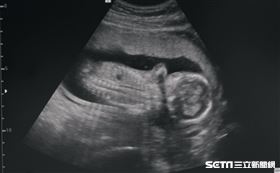

引產就是不愛?懷胎20週孕婦吐煎熬

「媽媽,我們剛剛做的超音波,發現你們的寶寶有唇腭裂的...